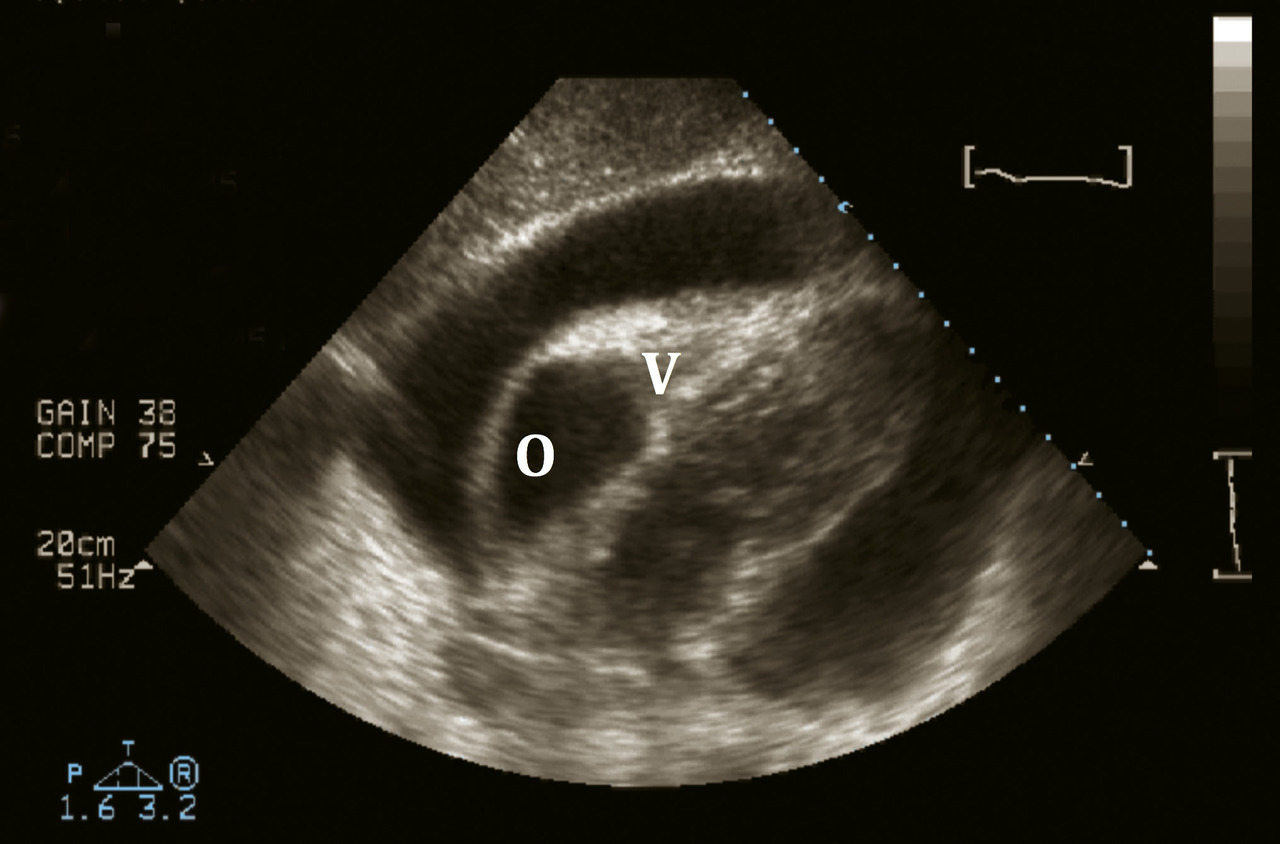

Tamponnade

La tamponnade correspond à la compression des cavités droites par un épanchement péricardique (fig. 3). Il s’agit d’une urgence médicale. Le diagnostic repose sur les signes d’insuffisance cardiaque droite : turgescence jugulaire, pouls paradoxal. Il peut y avoir des signes de choc : hypotension, vasoconstriction périphérique.

Elle complique exceptionnellement une forme virale bénigne. Elle se rencontre plus volontiers dans un contexte de cancer, tuberculose, insuffisance rénale chronique dialysée, traumatisme, complication de geste endovasculaire (coronarographie, pacemaker...), rupture post-infarctus...

En échographie cardiaque, épanchement abondant avec reten­tissement sur les cavités cardiaques droites.

La tamponnade correspond à la compression des cavités droites par un épanchement péricardique. Un remplissage par sérum salé isotonique doit être initié pour maintenir la pression des cavités droites. Si l’épanchement survient dans les suites d’une chirurgie thoracique, la reprise chirurgicale pour drainage est la règle, car elle permettra de refaire un point sur l’hémostase locale. En dehors de ce contexte, le drainage peut également être réalisé par ponction guidée sous échographie. La voie d’abord la plus classique est la voie sous-xiphoïdienne. Selon la description de l’épanchement en échographie, une voie apicale peut être envisagée.